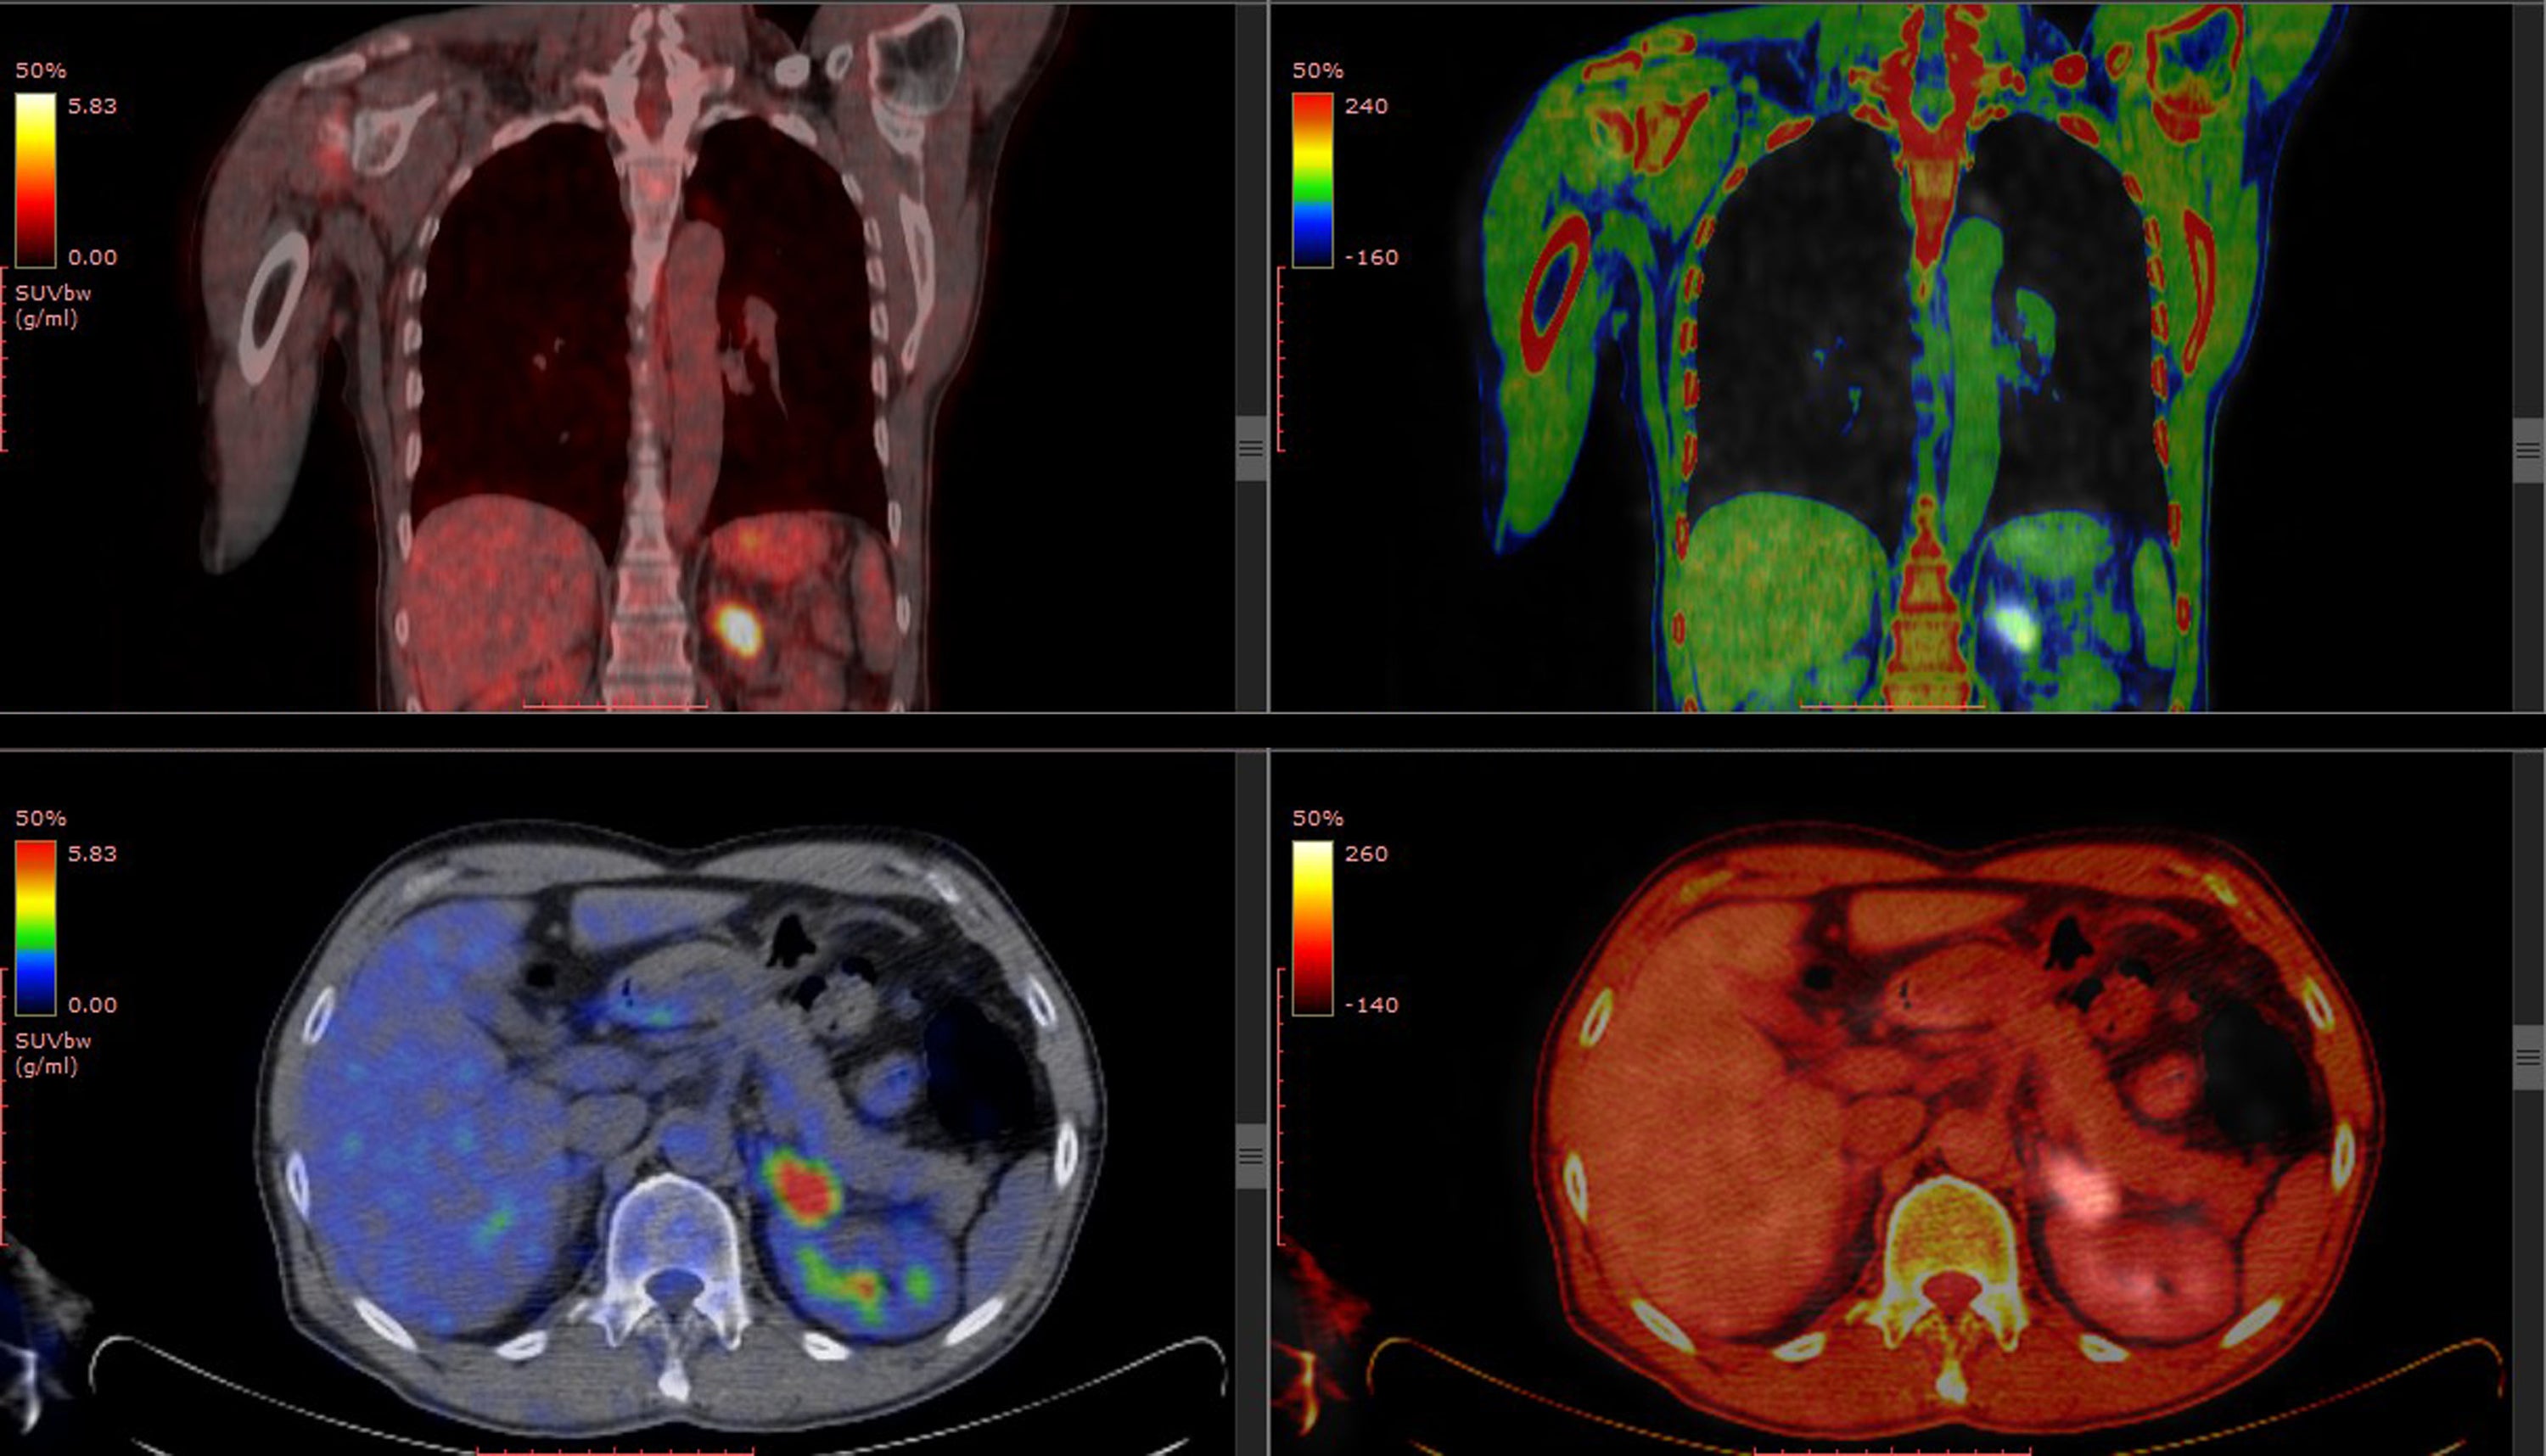

放射線診断専門医 核医学専門医 PET核医学認定医

病院で常勤医師として勤務しながら、2003年より当時黎明期であった遠隔画像診断を始める。現在は遠隔画像診断の専門医として年間1万件の診断を行っており、自社のサービス「画像診断ラウンジ」(https://radiology-lounge.com/)で遠隔画像診断を受け付けている。